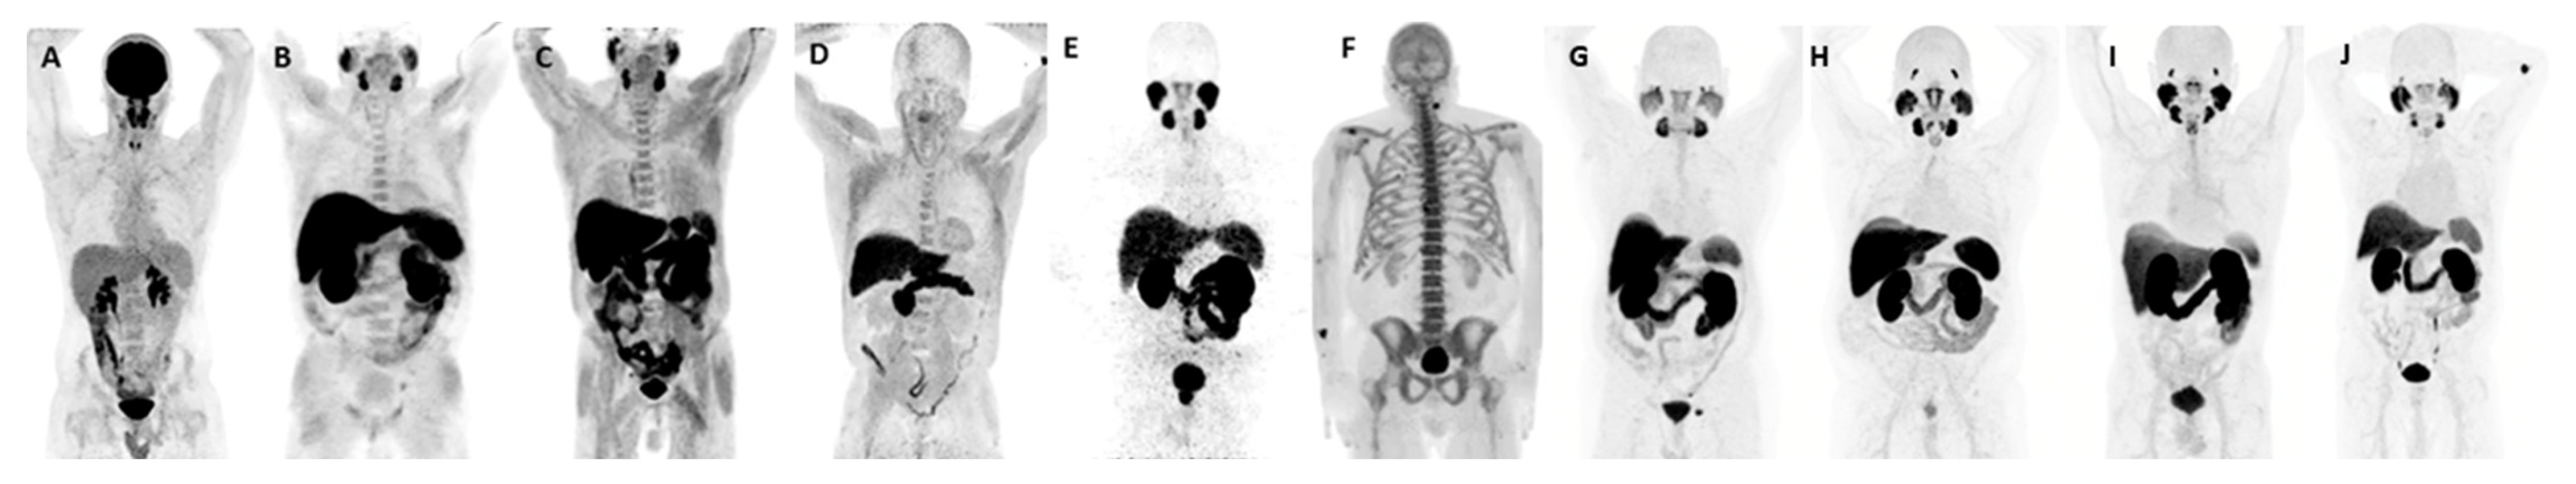

| Radiotracer | Sensitivity | Specificity | Comments |

|---|---|---|---|

| 18F-FDG | + | + | Limited sensitivity; highly nonspecific, given uptake in inflammation. |

| 18F/11C-Choline | +++ | ++++ | Good sensitivity in patients with PSA values > 2.0; specificity improved from 18F-FDG and 18F-NaF. Limited specificity due to mild uptake in inflammation and infection and uptake in non-prostate malignancies and other benign processes. |

| 18F-NaF | ++ | + | Highly sensitive for the detection of bone metastases; however, has no role in the detection of soft-tissue lesions; highly nonspecific, given uptake in benign sclerotic lesions. |

| 18F-Fluciclovine (FACBC) | ++++ | +++ | Increased sensitivity in comparison to 18F/11C-Choline; limited specificity due to mild uptake in inflammation and infection and uptake in non-prostate malignancies and other benign processes. |

| 68Ga/18F/64Cu-PSMA-11 18F-DCFPyL 18F-PSMA-1007 18F-rhPSMA-7.3 | +++++ | +++++ | Increased sensitivity in comparison to 18F-Fluciclovine. False negatives in PSMA non-expressing prostate cancer (approximately 10% of prostate cancers); specificity slightly limited in patients with benign osseous lesions (particularly 18F-rhPSMA-7.3 and 18F-PSMA-1007) and uptake in non-prostate malignancies and other benign processes. |

| 68Ga-DOTA-Bombesin | +++ | ++++ | Data remain limited; however, promising alternative in cases of PSMA-negative disease. |